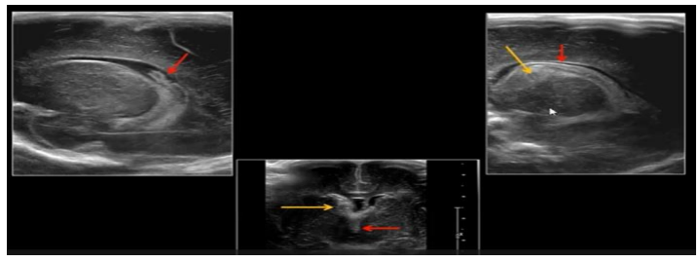

Qual a classificação baseada nas imagens, levando em consideração a classificação de Papile e cols?

A

I

B

II

C

III

D

IV